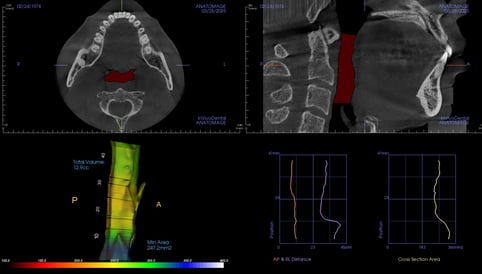

術前評估

- 齒列排列不整,牙弓偏窄

- 咬合接觸不均,後牙支撐不足

- 下顎位置偏後,口咽空間受限

- 夜間磨牙,顯示咬合與肌肉代償

- AHI:24.9(中度阻塞型睡眠呼吸中止症)